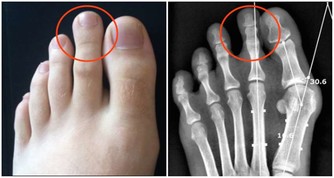

牙垢也叫牙菌斑,是附著在牙齦冠部、頸部及牙縫間的污垢。

牙垢主要是食物殘渣、口腔黏膜脫落的上皮、唾液及細菌混合而成。

牙垢久積,容易鈣化成牙結石。

2. 牙周疾病。牙垢久積,容易形成牙結石,牙石的存在會妨礙口腔衛生,促使菌斑更多地形成,

牙石本身也會吸附更多的細菌和毒素,造成牙齦充血、水腫,產生牙齦炎、牙周炎等問題;